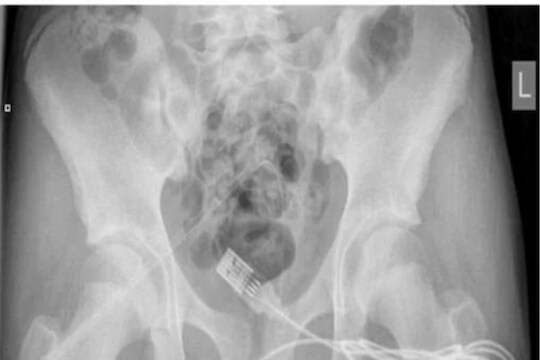

पंधरा वर्षाच्या या मुलानं आपल्या प्रायव्हेट पार्टमध्ये USB केबल टाकली होती. डॉक्टरांनी सर्जरी करून ही केबल बाहेर काढली. ही तार आतमध्ये अडकली होती. तारेला अनेक गाठी होत्या. या घटनेतील मुलाची ओळख लपवली गेली आहे. मात्र, डॉक्टरांनी सांगितलं, की हा मुलगा आपल्या प्रायव्हेट पार्टची लांबी मोजण्याचा प्रयत्न करत होता. मात्र, त्याचा हा प्रयोग अपयशी ठरला आणि तार आतमध्येच अडकली. या प्रकरणी मिळालेल्या माहितीनुसार, मुलानं स्वतःच ही तार काढण्याचा भरपूर प्रयत्न केला. मात्र, या दरम्यान त्याच्या प्रायव्हेट पार्टमधून भरपूर रक्तस्त्राव होऊ लागला. जेव्हा परिस्थिती जास्तच बिघडली तेव्हा त्यानं आपल्या कुटुंबीयांना याबाबत माहिती दिली. यानंतर तात्काळ त्याला रुग्णालयात दाखल करण्यात आलं.सुरुवातीला रुग्णालयातील स्टाफनं ही तार खेचून बाहेर काढण्याचा प्रयत्न केला. मात्र त्यात गाठ असल्यानं ती बाहेर आली नाही. अखेर सर्जरी हाच पर्याय उरला.

लंडनच्या युनिव्हर्सिटी कॉलेज रुग्णालयात (London University College Hospital) या मुलाची सर्जरी केली गेली. यादरम्यान मुलानं आपल्या आई-वडिलांसमोर डॉक्टरांना सांगितलं, की तो आपल्या प्रायव्हेट पार्टची साईज मोजत होता. याच दरम्यान तार आतमध्ये अडकली. सर्जरीदरम्यान ही केबल आतमध्येच कापली गेली आणि नंतर बाहेर काढण्यात आली. डॉक्टरांनी सांगितलं, की अशी अनेक प्रकरणं समोर येतात ज्यात मुलं उत्सुकतेच्या भरात अशा गोष्टी करतात. पालकांनी आपल्या मुलांवर नजर ठेवणं गरजेचं आहे, जेणेकरून पुढे अडचणी येणार नाहीत, असा सल्ला डॉक्टरांनी दिला.